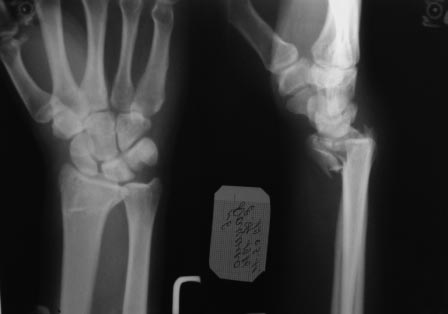

Скорей всего у Вашего пациента перелоп Barton-а

Порекомендую волярный срединный доступ (осторожно выделите n.medianus!), oстеосинтез АО малой 3,5мм Т-образной волярной пластиной, если есть locking plate - еще лучше! Pри ушивании - ни в коем случае не сшивать карпальную поперечную связку!- будет компрессионная нейропатия n.medianus !

Неплохо было бы выставить информацию о возрасте? А так доступ волярный, фиксатор любой из DVR.

Переломы волярной пластины (ладонные) со смещением относится к нестабильным переломам и удержать подвывих кисти можно только волярной (Butress) пластиной. Одной из первых пластин для лечения дистальных переломов луча

является DVR Hand Innovation (сегодня DePuy)

Сегодня все компании: Synthes, Stryker, Zimmer, Acumed, TriMed и т.д. имеют пластины для фиксации дистального перелома лучевой кости. На снимке метод фиксации дистальных переломов, справа Stryker, а слева пластина Synthes,

женщина 58 лет, политравма.